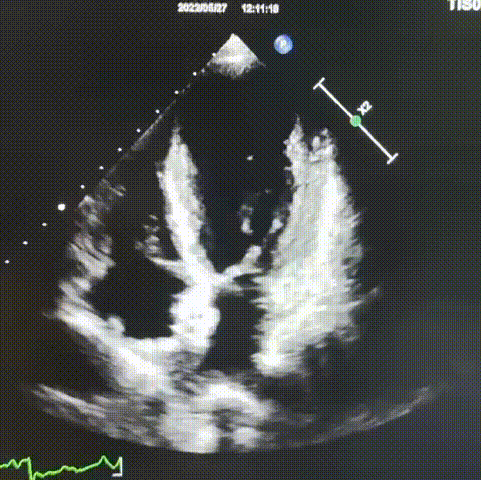

术前超声